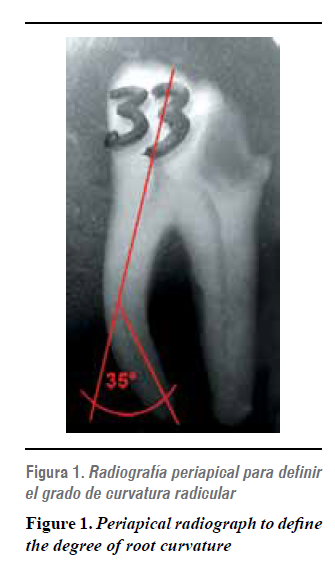

Los canales curvos fueron definidos por Schneider en el año 1971 como el ángulo formado por la proyección del eje dentario y la tangente del ápice radicular, según el ángulo se clasifican en tres categorías: leve (9º o menos), moderada (entre 10 y 24º) y severa (25 a 70º).8

- Curvaturas radiculares entre 25 y 35°, de acuerdo con el coeficiente de curvatura de S. W. Schneider,8 para estandarizar la muestra con respecto a esta variable.

A los molares preseleccionados mediante inspección morfológica, se les tomó una radiografía convencional para verificar la permeabilidad y la curvatura de los conductos según criterio de inclusión (figura 1) .